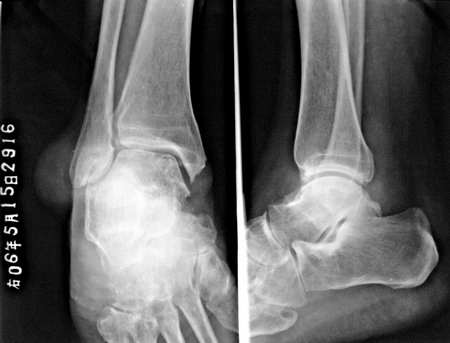

痛风,外踝之软组织肿物?

痛风,外踝软组织肿块影呢

痛风所致关节病变,软组织肿块为通风形成的皮下结节

支持痛风---穿凿状破坏,软组织肿块,痛风石形成。

穿凿样骨质破坏及及足、外踝痛风结节形成符合痛风性关节炎。

痛风,外踝之软组织肿物?经典!

痛风伴蜕变.踝关节处应该是软组织肿物吧.好象没有看到骨质吸收和压迫改变

尿酸高,该患者患病已经近十年,双手及双足均可见多发明显病变。